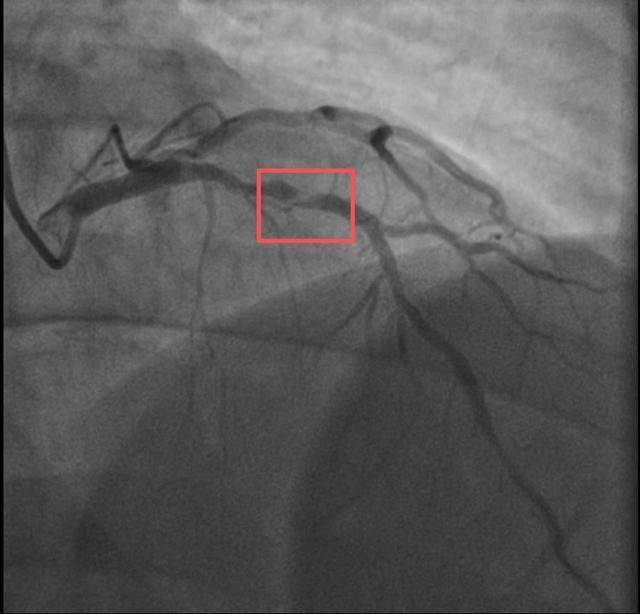

孙先生是一位羽毛球教练,身高173厘米,体重约90公斤。一年前,他因胸闷就诊,被查出心脏右冠中段、远端钙化斑块,以及前降支中段60%狭窄。尽管没有三高的危险因素,但可能有早发冠心病家族史。孙先生坚信通过运动瘦身可以扭转健康状况,因此拒绝了介入治疗,仅接受药物治疗。一年内,他的体重从96公斤减到了90公斤左右。然而,近期他在陪孩子打羽毛球时,亲自上场挥杆仅10分钟左右,就因心前区剧烈绞痛被送进了急诊。浙江医院心血管内科副主任汤益民主任医师分析,剧烈运动导致孙先生心脏的不稳定斑块破裂,造成前降支近段次全闭塞。所幸送医及时,经过紧急介入治疗,孙先生的身体险情被成功化解。